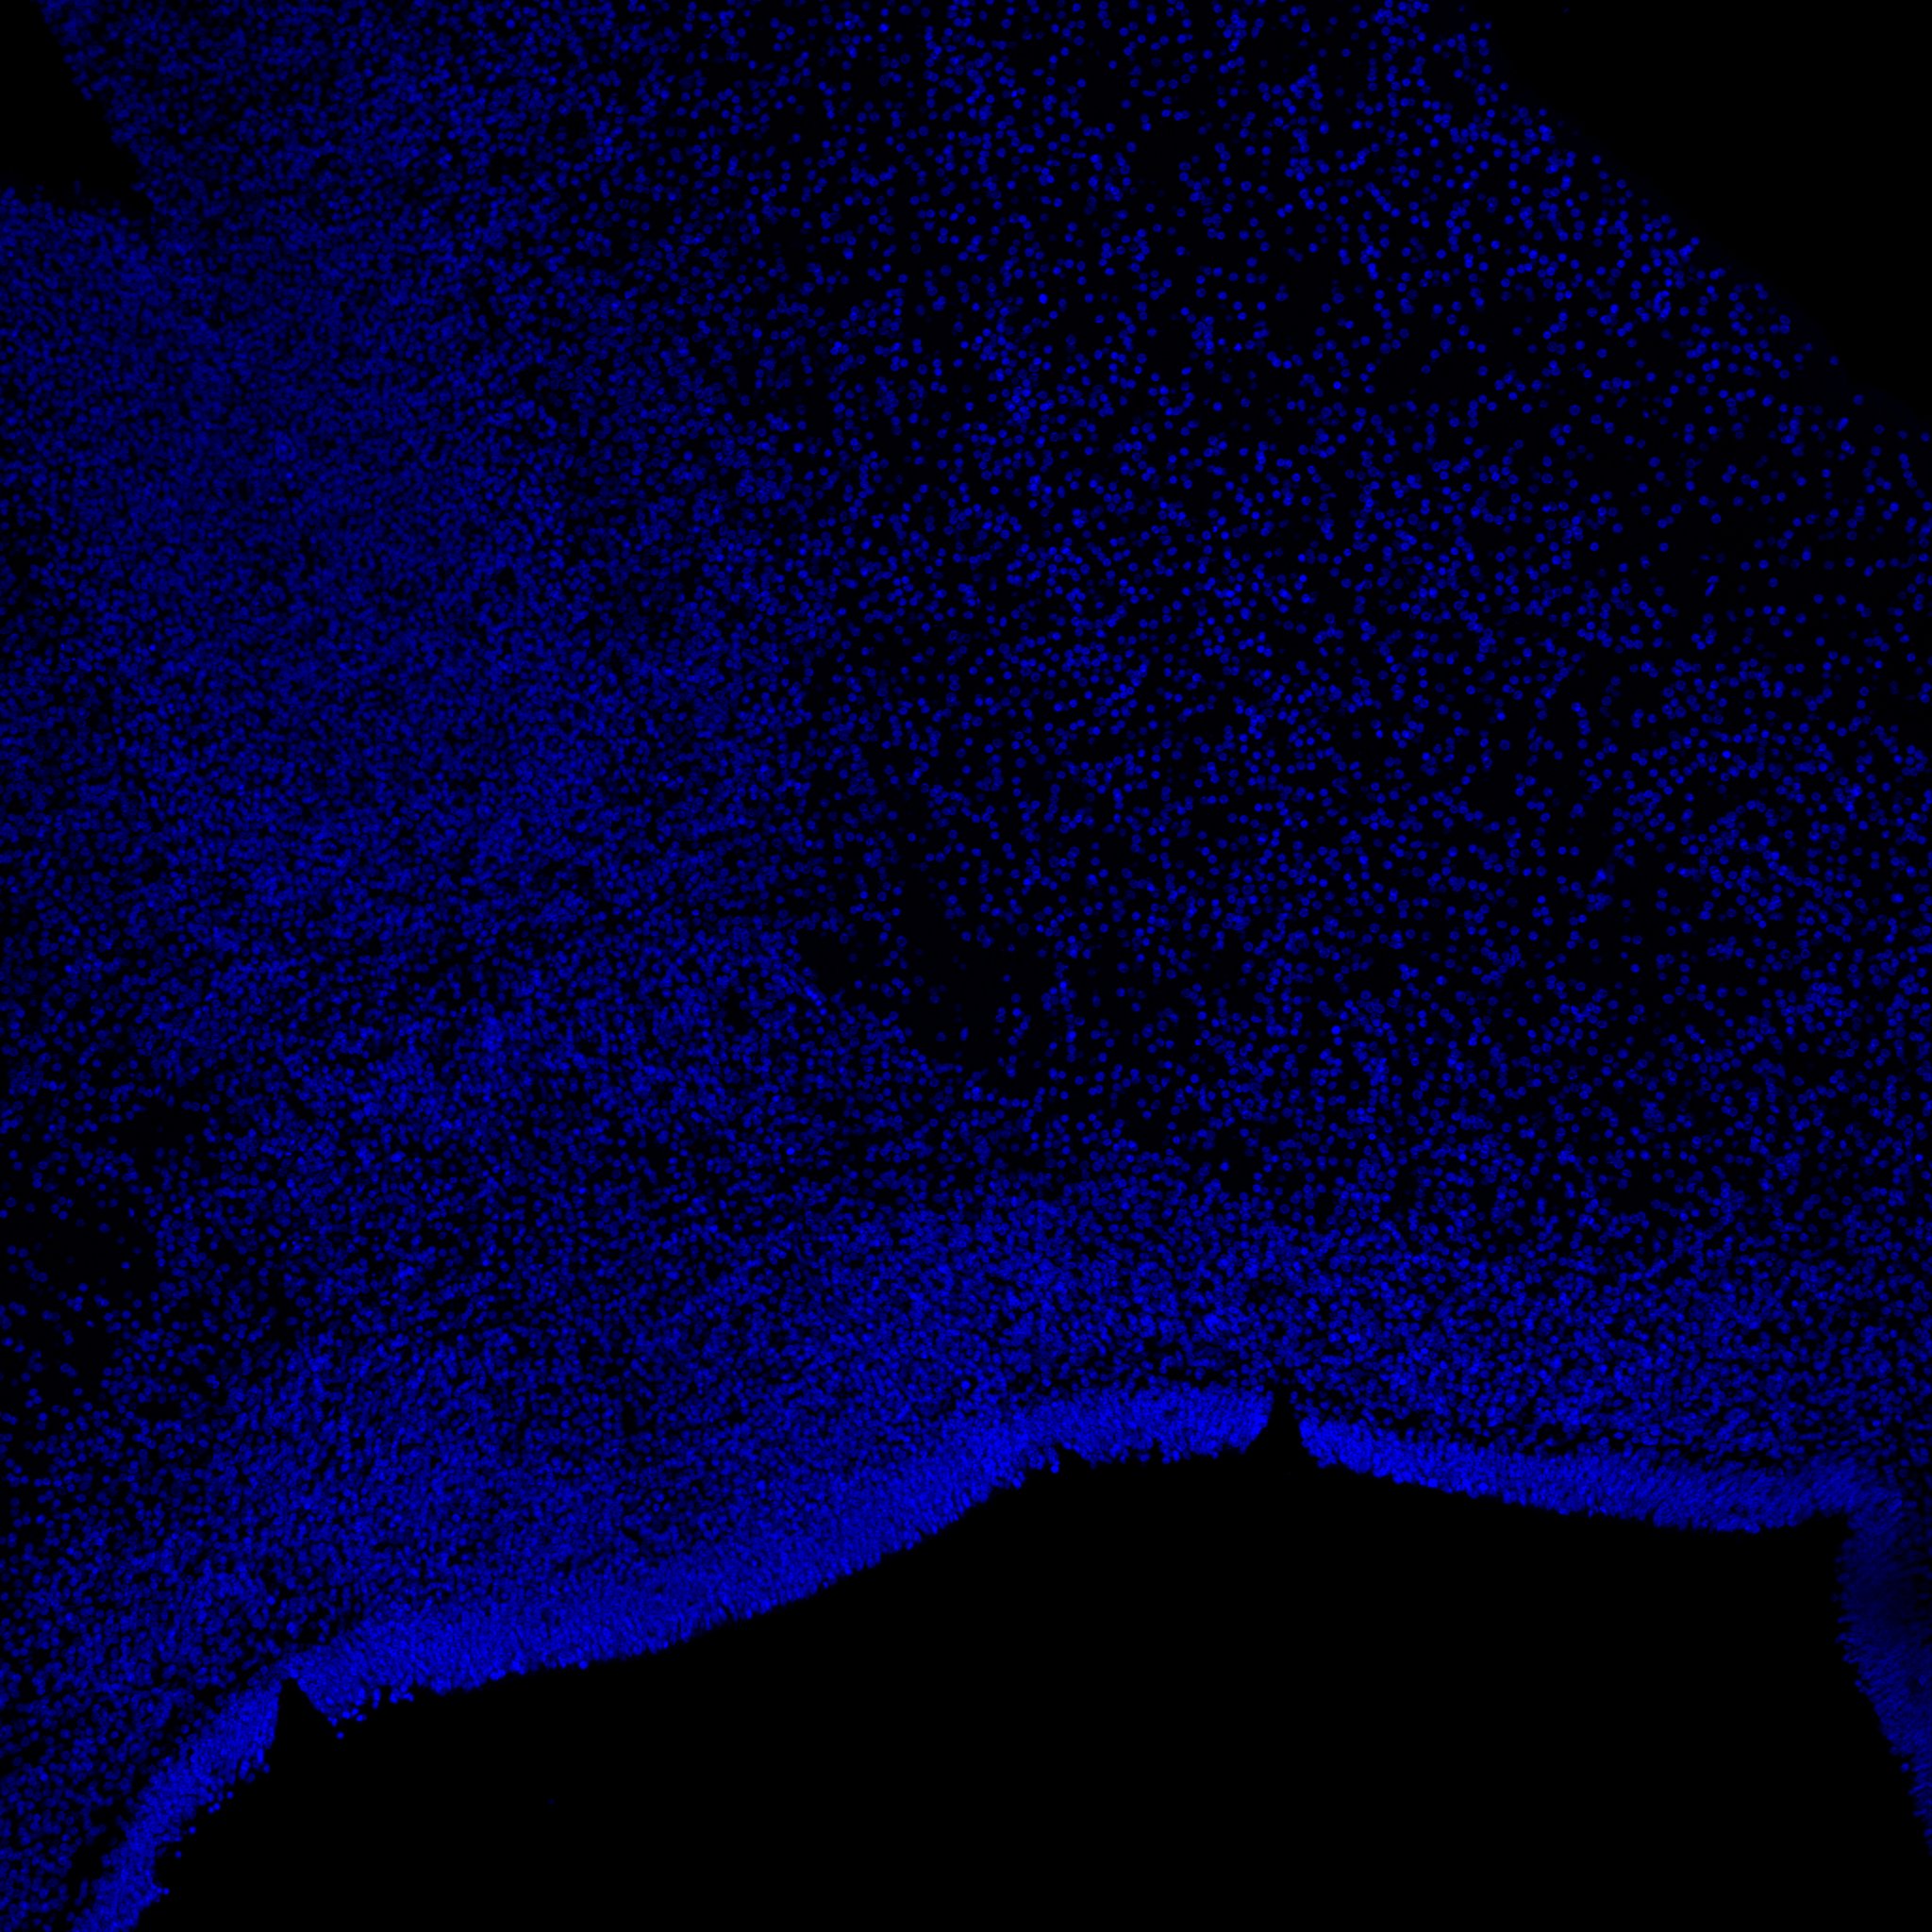

DAPI

6PCW human midbrain